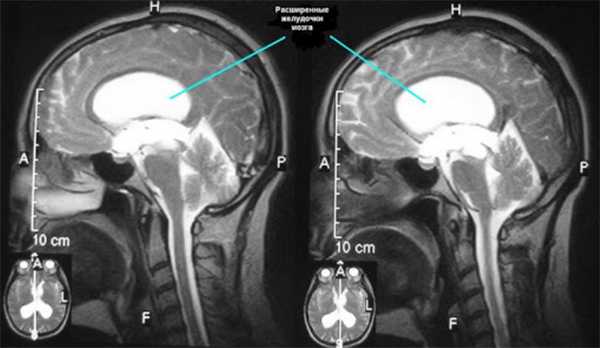

МРТ головного мозга. На МР-томограмме в сагиттальной плоскости отмечается расширение боковых желудочков мозга (линии), за счет повышенного содержания церебральной жидкости (ликвора).

МРТ при гидроцефалии головного мозга считается одной из наиболее информативных методов обследования, благодаря которому определяют не только локализацию патологических изменений, но и причину нарушения оттока ликвора. На снимках врач-рентгенолог видит аномальное увеличение количества церебральной жидкости (ликвора) в желудочках мозга, субарахноидальных щелях, определяет повышенное внутричерепное давление.

МРТ позволяет провести детальную оценку всех структур головного мозга, распознать следующие патологические изменения:

степень увеличения и расширения желудочков;

количество и локализация цереброспинальной жидкости;

изменение структуры мозговой ткани;

увеличение объема субарахноидальных пространств;

поражение стволовых структур;

мозговые образования (опухоли, кисты, кровоизлияния).

МР-диагностика с высокой долей достоверности определяет патологические процессы, проявившиеся на фоне нарушения оттока ликвора. Благодаря получению многоплоскостных изображений на МРТ исключаются сопутствующие изменения вещества головного мозга. Врач диагност при гидроцефалии на снимках заметит следующие изменения:

увеличение объема боковых желудочков;

снижение МР-сигнала от субарахноидального пространства, уменьшение конвекситального субарахноидального пространства;

локальное выпячивание боковых желудочков.